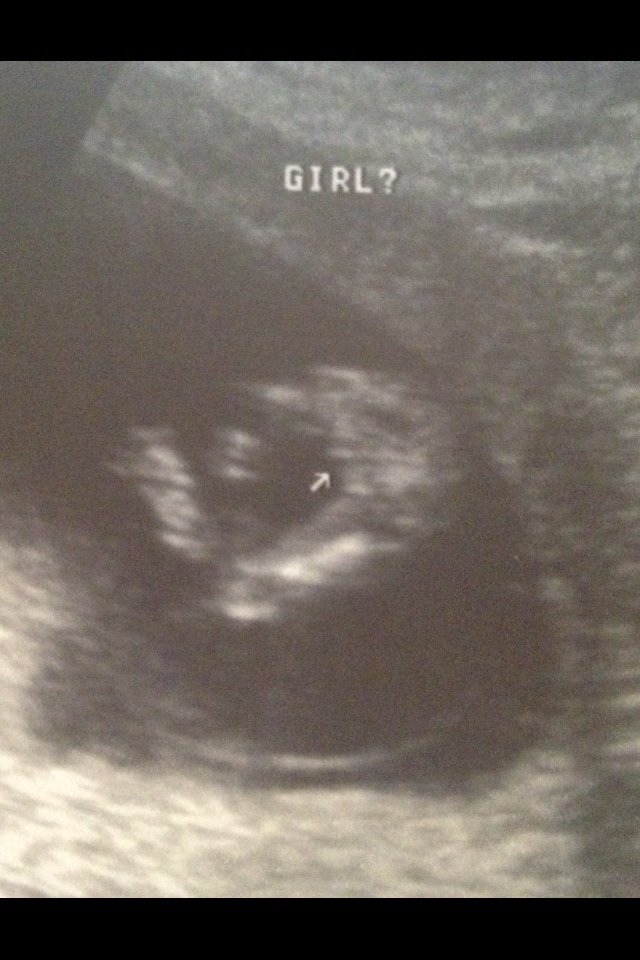

15 week ultrasound and it's a......